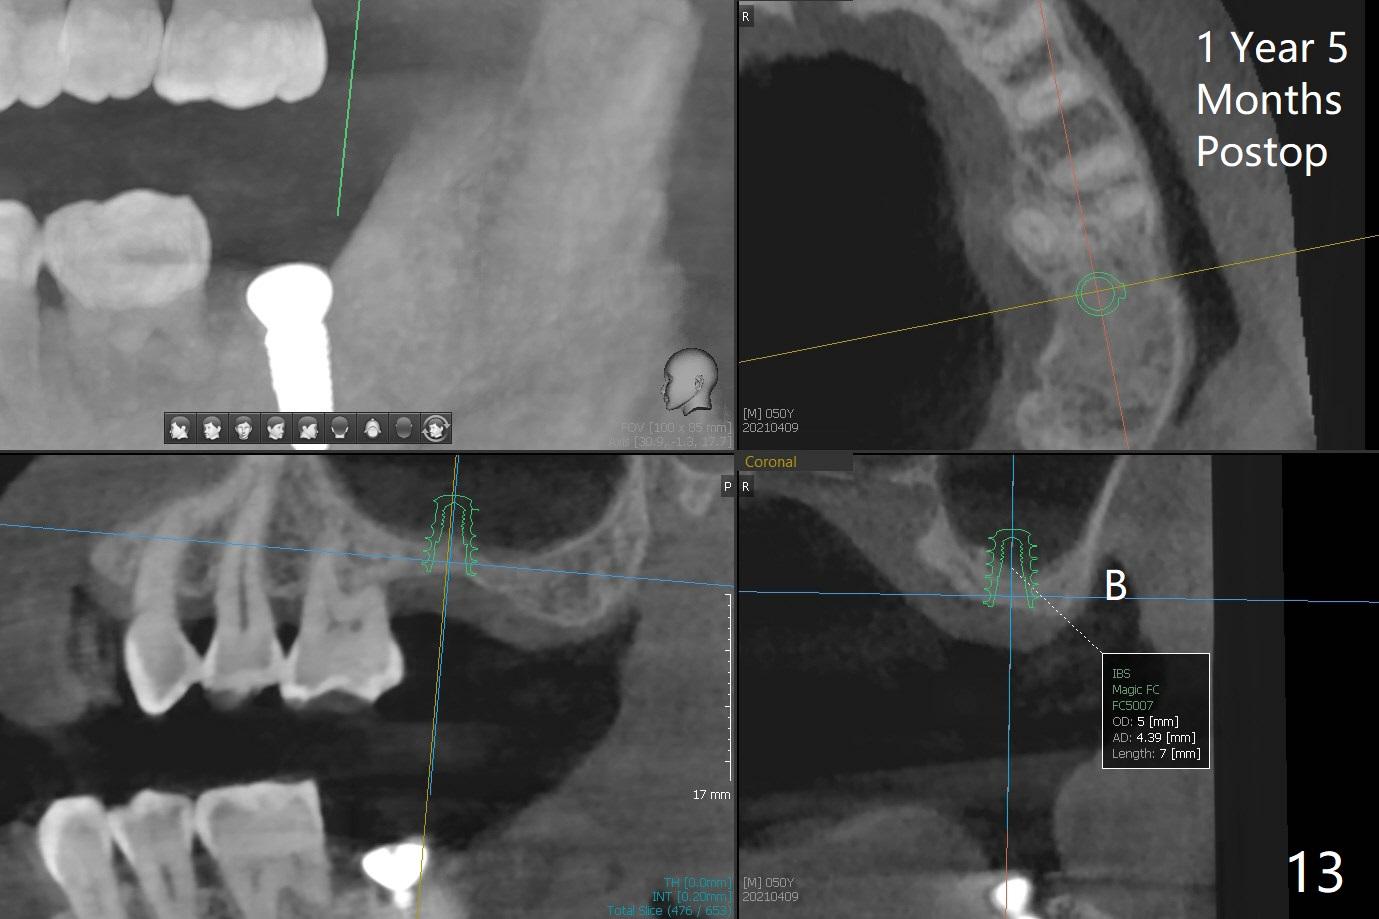

After 4.5x7.3 mm drill with 3 O-rings at #15, use 2.2x7.3 mm one with 2 O-rings. The sinus floor feels like to be perforated, but perio probe does not find the perforation. Nose blowing does not reveal air leakage. It seems fine when 3.0x7.3 mm one with 2 O-rings is being used. The sinus membrane perforates when Magic Sinus Lifter is used. Mixture of autogenous bone (from drills) and allograft does not stick to the periosteal elevator (Fig.1). Forty-minute centrifuge leads to separation of serum (Fig.2 S) from Red Blood Cell layer (R). The separation of the top tube is incomplete with RBC invade the serum layer in a few second (Fig.3 arrow). While the serum layer of the bottom tube is prepared for PRF membrane, a part of the serum layer of the top tube is withdrawn to make sticky bone (Fig.4). The top tube returns to the centrifuge for another 30 minutes to make the second PRF membrane. The first PRF membrane is inserted into the osteotomy and pushed into the sinus with empty feeling, followed by the sticky bone and last by the 2nd PRF membrane. A 5x7.3 mm implant is placed with ~ 10 Ncm, followed by a 6.8x4 mm healing abutment (Fig.5,6 (retrospectively healing screw should be used to reduce sinus-oral communication)). There is no mushroom in the sinus, but hopefully the sticky bone will stick to the bottom of the sinus for maturation. Sinus surgery precaution is provided. Next time tap or dummy implant will be used for sinus lift after initial osteotomy with guide. In fact the patient with diabetes under control has mild cold. The procedure should have been canceled. There is no postop nasal hemorrhage or discharge. The patient returns nearly 8 months postop. The wound is infected. The healing abutment is changed to a healing screw with oral antibiotic. Two weeks later, the area remains infected with symptoms (Fig.7-9). The healing screw is not covered completely. After implant removal, the sinus membrane is perforated. A piece of collagen plug (preferably Osteogen plug) is inserted (Fig.10,11). Because of the concavity, bone graft seems necessary when the wound heals. One week later, perimplantitis develops at #2. The patient is ready for the 3rd placement 1 year 5 months post last implant removal (Fig.12). The bone is 1.8 mm thick, apparently composing of 2 fused cortical plates. Make an incision for both external and internal sinus lift with retraction. Find the old guide to start osteotomy including bone trimmers and use Magic Lifter. If the membrane is broken, open the lateral window to repair with PRF.